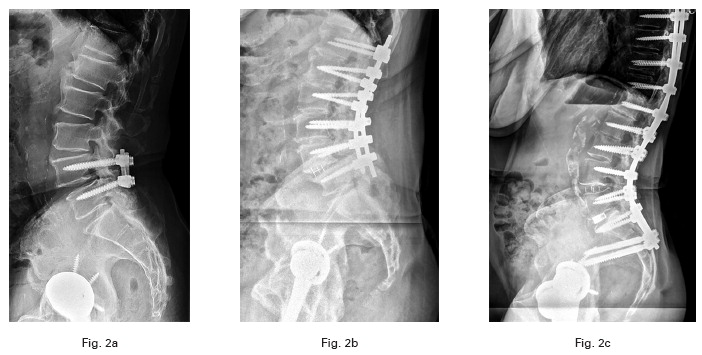

La fusión lumbar que afecta al sacro aumenta el riesgo de luxación en la artroplastia total de cadera primaria

- Las fusiones espinales lumbosacras antes de la ATC aumentan el riesgo de dislocación en los primeros seis meses.

- Las fusiones que afectan al sacro con múltiples niveles de afectación lumbar aumentaron notablemente el riesgo de luxación posoperatoria en comparación con un grupo de control y otras fusiones lumbares.

- Los cirujanos deben tener cuidado con la colocación de los componentes y pueden considerar implantes de mayor estabilidad en esta cohorte de alto riesgo.